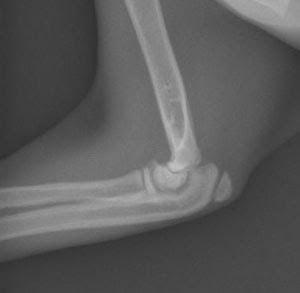

یکی از این موارد مشکوک بودن به شکستگی اندام ها در کودکان و نوجوانان است.

چون در این سن استخوان ها هنوز در حال رشد هستند خطوط اپی فیزیال از انتهای اندام ها جدا به نظر می رسند و این می تواند باعث تشخیص نادرست پزشک شود.در چنین موردی باید یک عکس دیگر از اندام مقابل گرفته شود.

خودم چند مورد دیده ام که مثلا آرنج بچه ای ضربه خورده است و پس از عکسبرداری پزشک درتشخیص شکستگی دچار اشتباه شده است و دستور گچ کرفتن داده است.در صورتی که شکستگی در کار نبوده است.لذا در این گونه موارد عکسبرداری مقایسه ای واقعا به کار می آید.

یادمان باشد هر گردی گردو نیست و هر خط شکستگی ، شکستگی نیست.